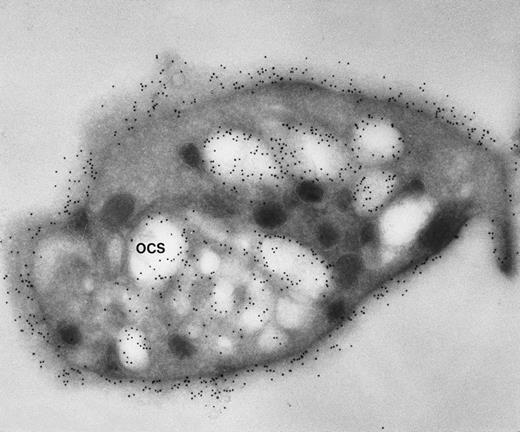

Frozen thin section of a CB-treated normal discoid platelet stained by the immunogold technique for GPIb/IX. The gold particles coupled to anti-IgG are 10 nm in diameter. Dilated OCS channels are as heavily stained by gold particles indicating sites of GPIb/IX as are present on the exposed surface. (Original magnification ×44,000.)